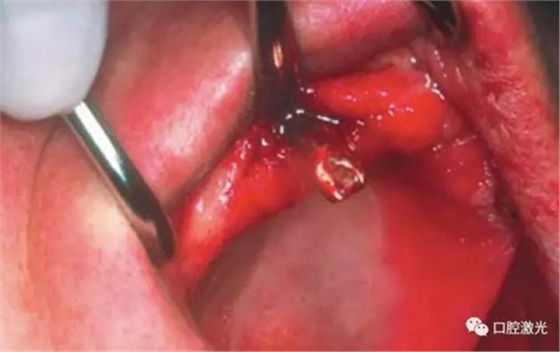

對(duì)患者實(shí)施局部麻醉,隨后在種植體位置進(jìn)行翻瓣。利用塑料刮治器將肉芽組織清除干凈,并將翻瓣邊緣削薄。此時(shí)在種植體周圍可見(jiàn)明顯骨缺失。

利用半導(dǎo)體激光照射已經(jīng)暴露的種植體表面。激光輸出功率1.0W,連續(xù)模式,照射時(shí)間20秒,光纖芯徑400um,光纖尖不初始化。由于激光的選擇性吸收的特點(diǎn),該激光能量設(shè)定足以殺滅導(dǎo)致種植體周圍炎的厭氧菌,卻不會(huì)對(duì)種植體表面和種植體周圍生物組織(骨組織、黏膜組織)造成熱或者機(jī)械損害。在軟組織恢復(fù)6周和12周后分別再進(jìn)行一次激光滅菌治療(參照牙周炎激光滅菌程序)。